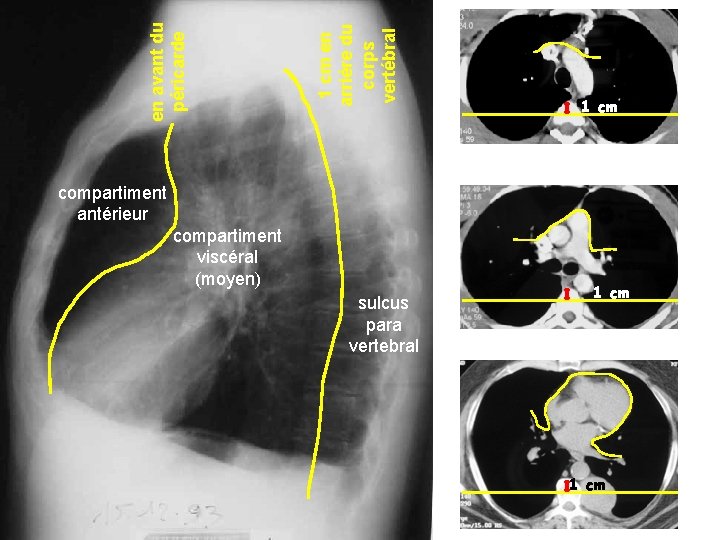

Pr Marquette. Année universitaire 2008 -2009 compartiment viscéral (moyen) sulcus para vertebral 1 cm en arrière du corps vertébral en avant du péricarde 1 cm compartiment antérieur 1 cm